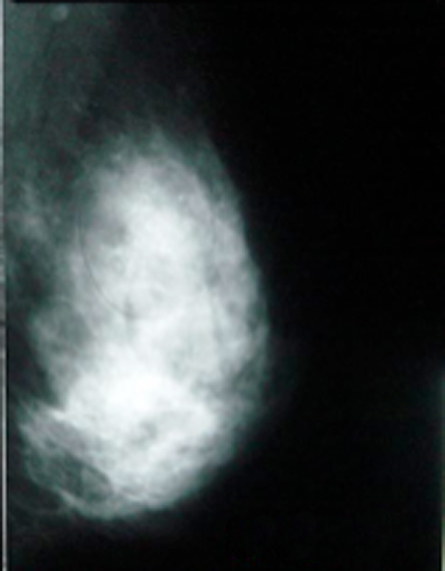

For all of its advantages, mammography misses some tumors and points out what appear to be cancers — but aren’t. That’s why physicians follow up suspicious mammograms using some adjunct technology. Usually magnetic resonance imaging, aka MRI scans. However, in recent years, a new technology — breast-specific gamma imaging, or BSGI — has been spreading in hospitals across the United States.

BSGI identified tumors among all 159 women who, owing to mammograms or breast self-exams, had a suspected cancer. In addition to the lumps that initially triggered this “second look,” BSGI also identified 56 additional apparent cancers. Although most of these proved benign, BSGI did pick up 23 true cancers that had been “occult” — not visible on mammography or self exams, often owing to their extremely small size.